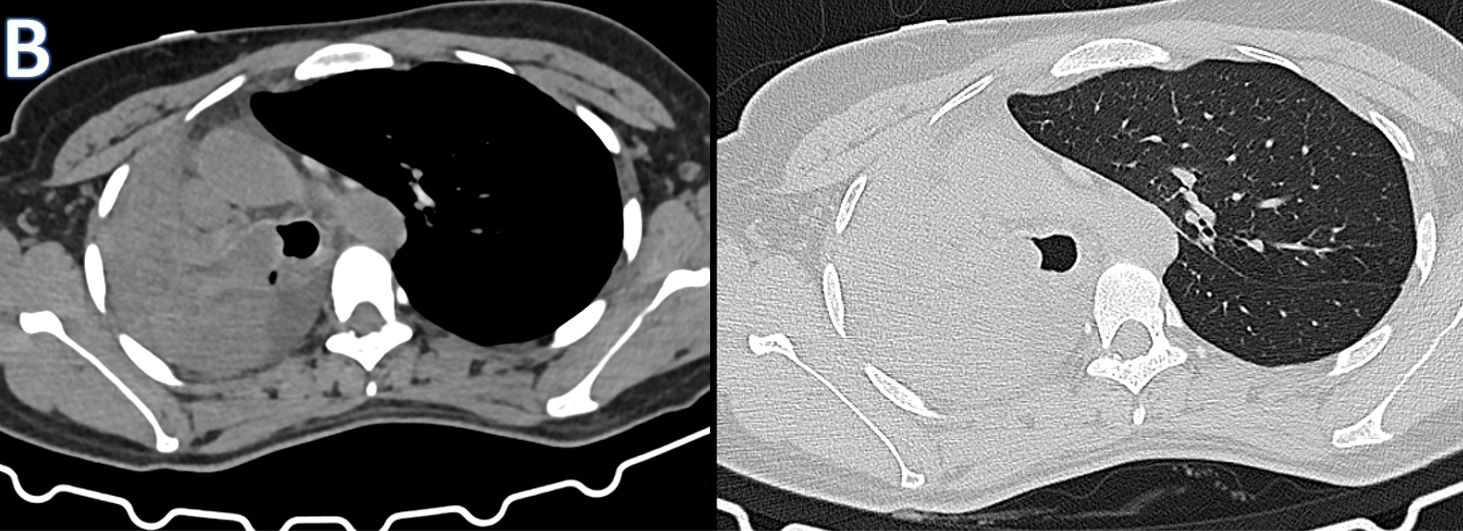

A - AP-Chest XRAY

• ARROW: Tracheal deviation to the Right.

• STAR: Opacified right hemithorax.

• Findings are consistent with Collapse of the right lung.